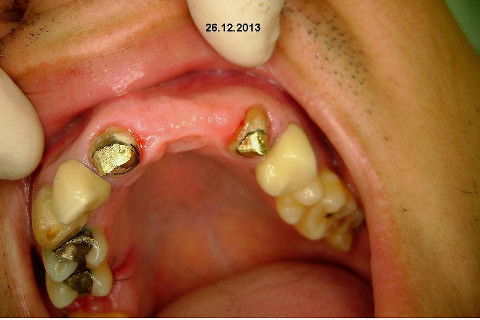

Paciente apareceu em meu consultório em dezembro/2013 para resolver problema de insatisfação com ponte fixa provisória anterior, realizada há 9 anos atrás (2004)...pretendia realizar somente a reabilitação em maxila/anterior, não contava com outros problemas com maior gravidade na sua boca, o máximo que citou foi a indicação para a exodontia do 16...